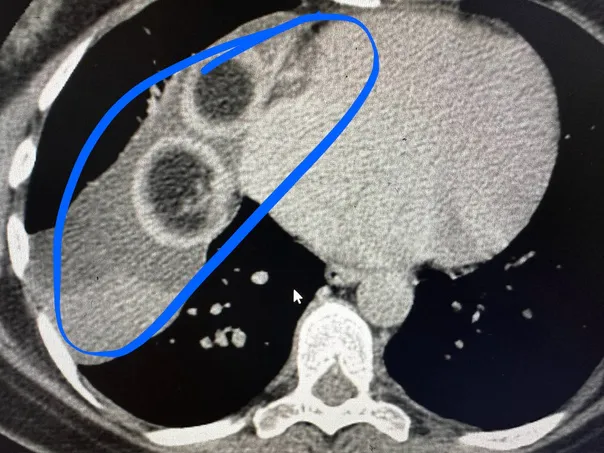

Как сообщили в медучреждении, дермоидную кисту с клубками волос внутри удалили хирурги торакального отделения №1 РКБ.Образование в средостении обнаружили у 44-летней жительницы Бавлинского района РТ на флюорографии, на КТ подтвердили. Оказалось, что рядом с сердцем выросла дермоидная киста размером 10 на 7 на 15 сантиметров. Внутри этой кисты обрадовались две большие волосяные головки. Образование удалили торакоскопически - через 3 прокола - за 2 часа. И в этот же день женщина уже ходила по палате.Врачи напоминают, что важно проходить флюорографию каждый год.